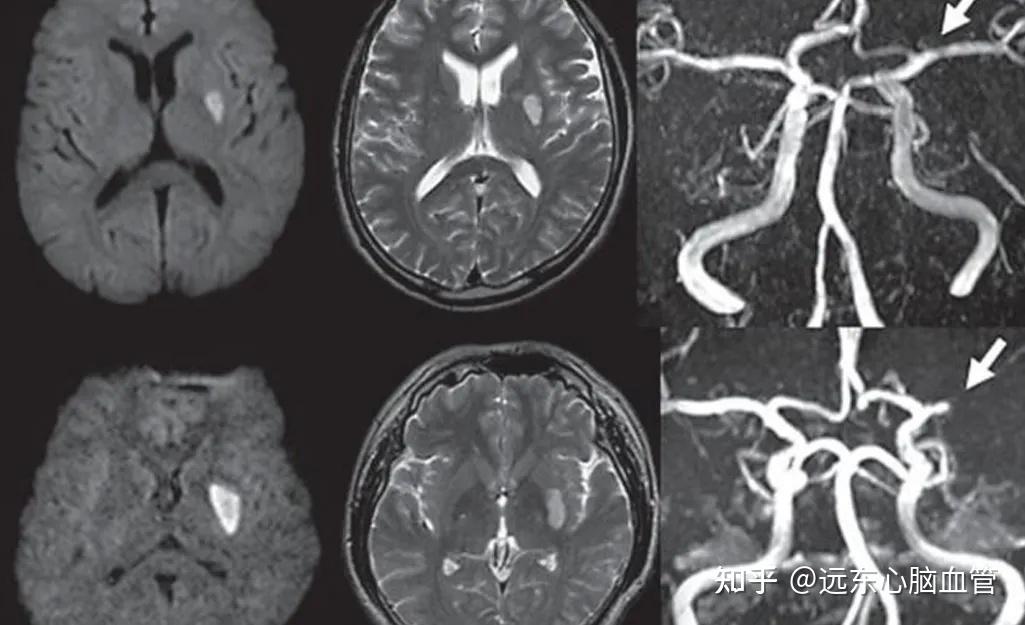

"腔梗"过,经常要疏通血管吗? - 知乎

图片尺寸1025x625